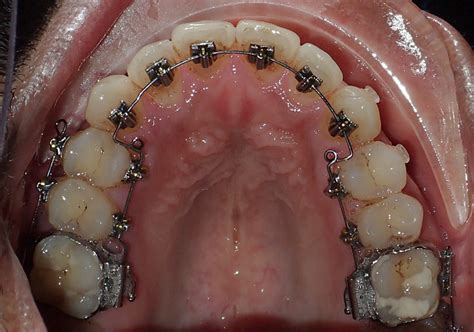

Mesial Distal Tooth Measurements Are Vital For Orthodontic Success

Mesial, Occlusal and Distal Decay – 10K Teeth